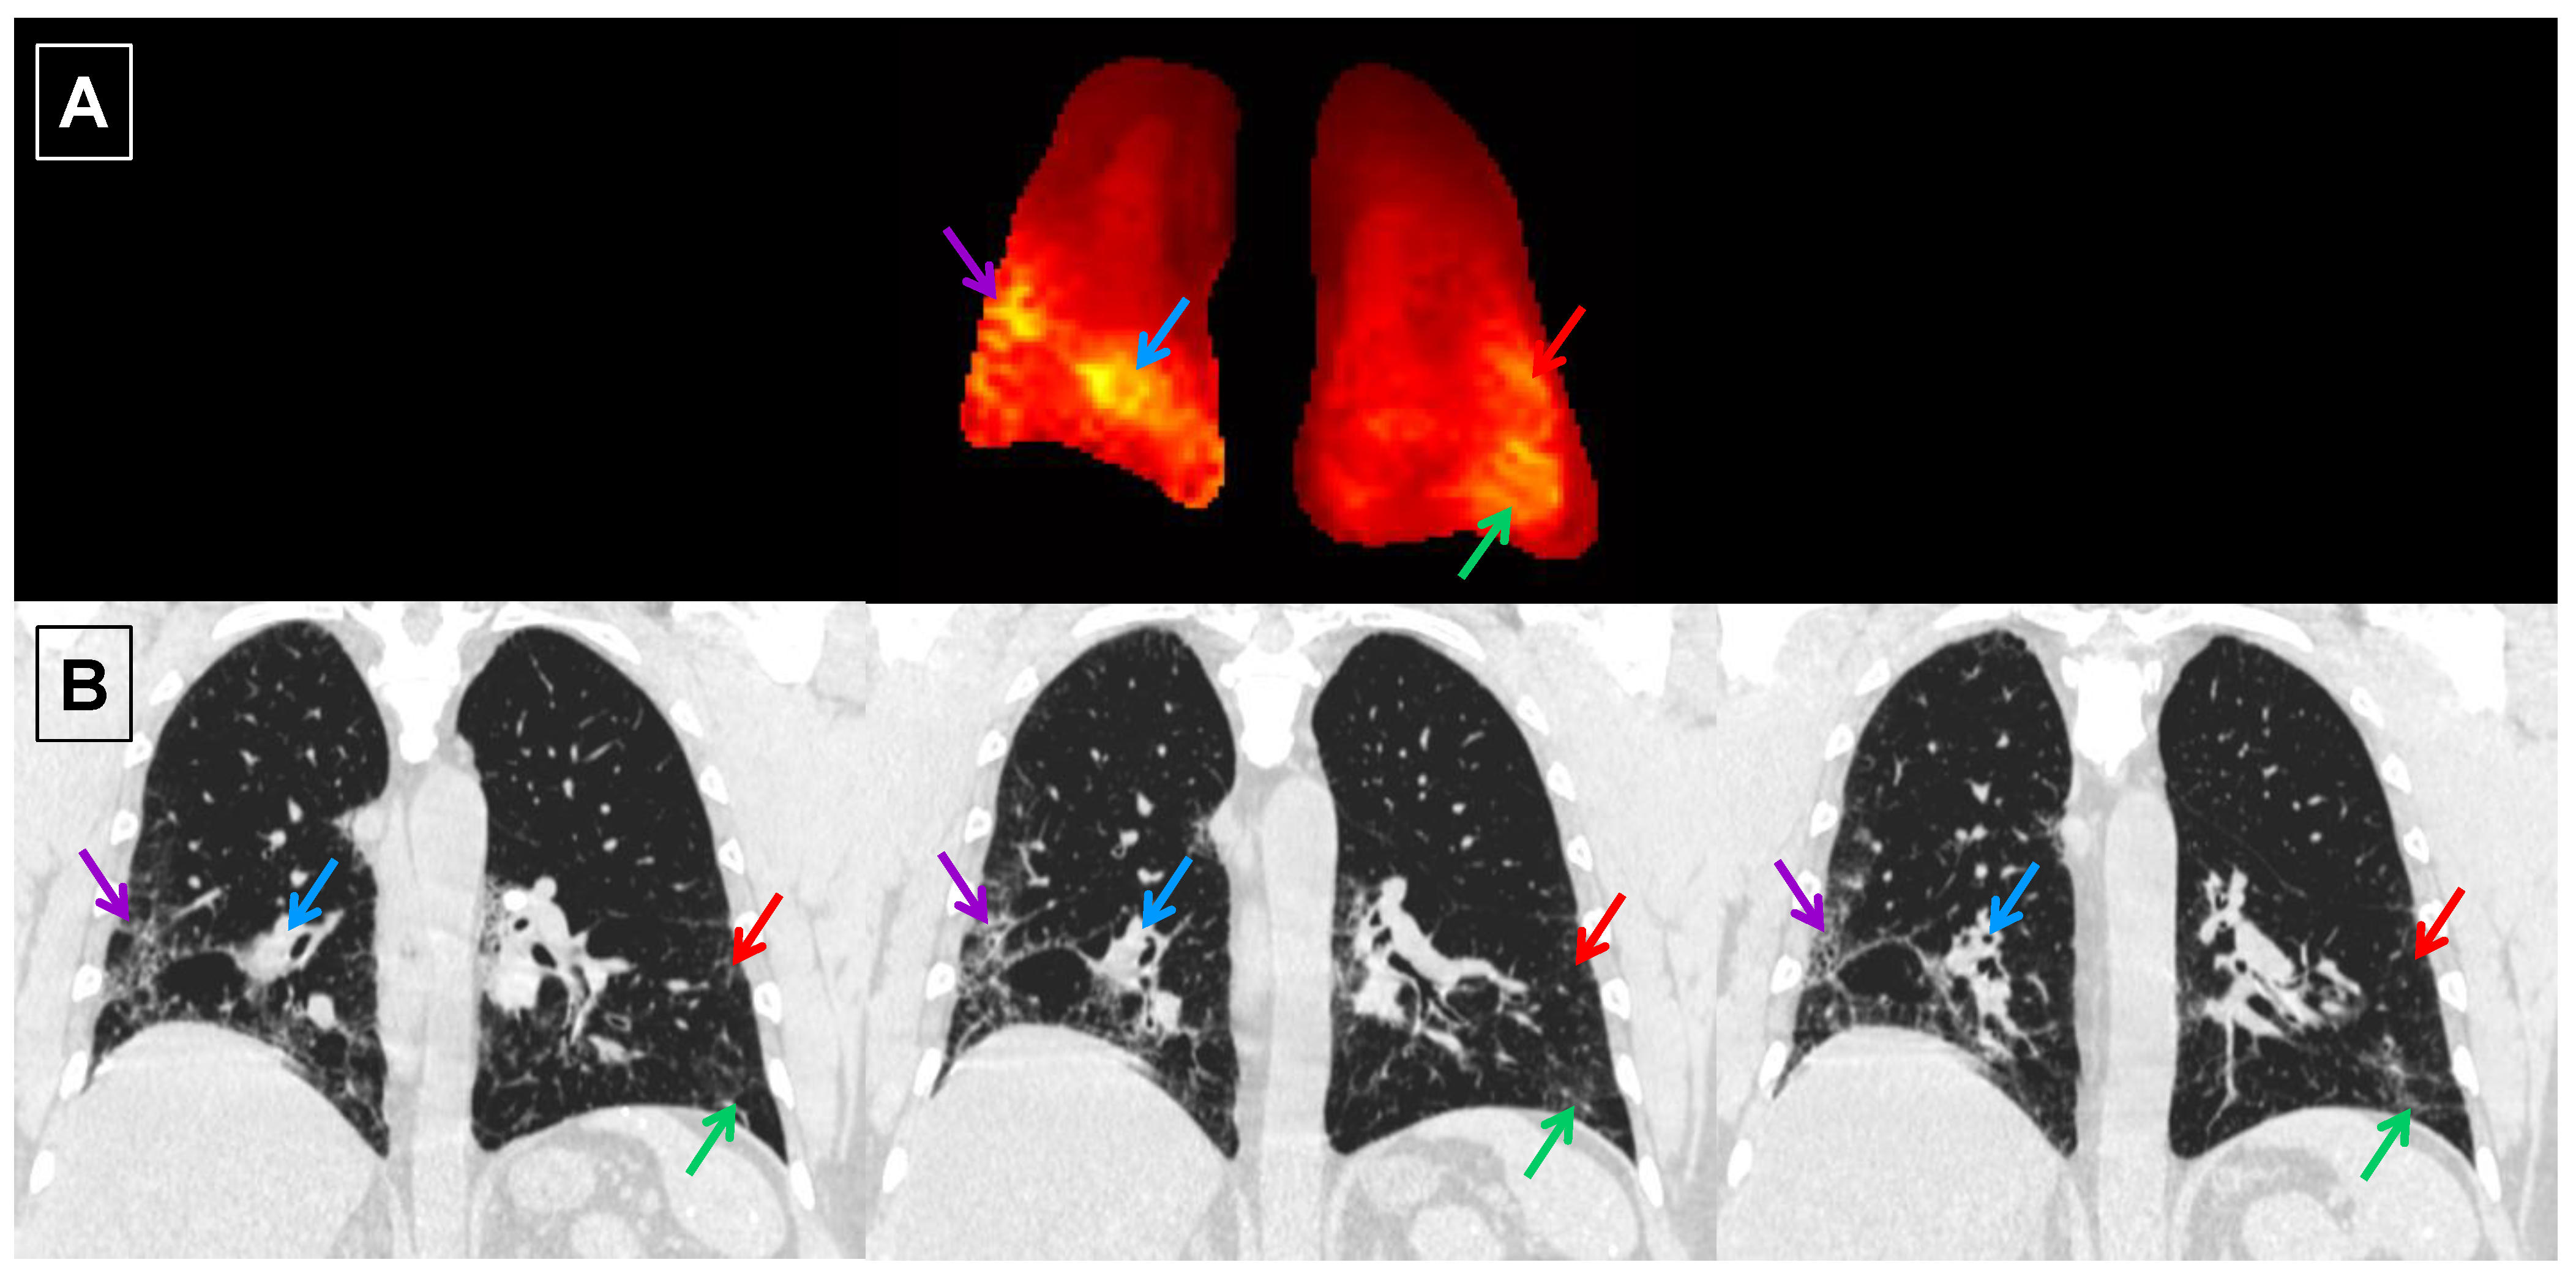

Figure 8.

Central coronal slice of the Tissue/RBC maps (A) and spatially matched coronal HRCT images (B) from IPF subject I6. Due to the difference in the slice thickness between the Tissue/RBC maps (15 mm) and HRCT images (0.7 mm), information from multiple nearby HRCT images could appear in a single slice of the Tissue/RBC maps. Each arrow points to a region of high Tissue/RBC, and the same color arrow points to the corresponding region of fibrosis in the HRCT images.

In order to correlate the HRCT regional findings with physiological maps from the 3D SBCSI, the CSI lung maps and data (Table 4) were divided into regions corresponding to the areas scored in HRCT (upper, middle, and lower thirds of lungs). Among the HRCT findings, RBC CS had the strongest correlation (R = −0.99) with all HRCT scores except emphysema, and there were very strong correlations among HRCT scores and Tissue CS, RBC-Tissue CS, Tissue T2*, and RBC T2* as well (Table 5). Furthermore, regions of high Tissue/RBC values at the base and periphery of the lungs were found to correspond well to regions of fibrosis in the HRCT images (Figure 8).

Ground-glass opacity scores (R = −0.40), including other HRCT scores, were not strongly correlated with the Tissue/RBC ratio, as shown in Table 5, which is consistent with the correlation between fibrosis scores and Tissue/RBC ratio found by Wang et al. [36]. However, regions of high Tissue/RBC ratios were well matched with regions of fibrosis in HRCT images (Figure 8). This agreement supports the observation that regional heterogeneities indicating gas-exchange impairment in Tissue/RBC maps were linked to fibrosis observed in HRCT images.